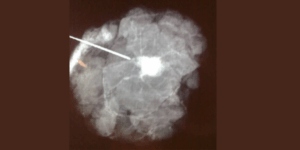

Breast Cancer Mammography